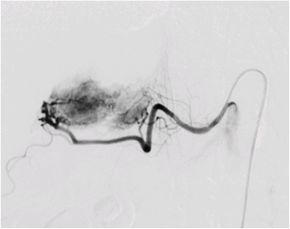

肝細胞がんに対する経カテーテル動脈化学塞栓療法の実際

大腿動脈(太ももの付け根の血管)又は上腕動脈の位置を確認し、消毒と局所麻酔を行い

ます。動脈を正確に穿刺してカテーテルを挿入し慎重に進めていきます。肝細胞がんを

栄養する血管が同定できたら、マイクロカテーテル(通常ものよりさらに細いカテーテル

)を栄養血管へ選択的に挿入し、腫瘍の近傍まで進め、そこから造影を行います。

次に肝細胞がんの径、腫瘍濃染、患者さまの全身状態、肝臓機能などを総合的に判断し

、マイクロカテーテルか治療後の造影では塞栓物質により肝細胞がんへの血流がなくな

っているので腫瘍は描出されません。

肝細胞がんを栄養する血管描出(塞栓前) 肝細胞がんを栄養する血管描出(塞栓後)

選択的動脈造影 上腸間膜動脈造影

当院では血管内治療とRFA治療を組み合わせて肝臓の機能を温存して体の負担が少なく、局所的で効果の高い治療を行っております。